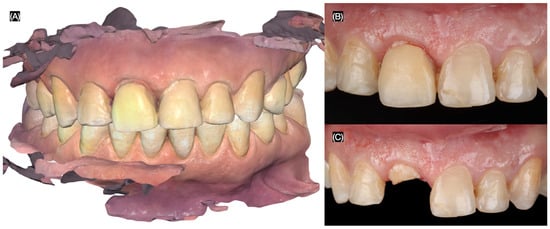

A 32-year-old female patient presented with the chief complaint of mobility in a front crown. She reported playing basketball and experiencing trauma to her mouth after being struck by the ball. Additionally, the patient expressed a desire to improve her overall smile esthetics. To begin the diagnostic process, intra-oral photos were taken, and an intra-oral scan (Medit i600, Seoul, South Korea) was performed for the maxillary and mandibular arches, including an occlusal registration to capture the bite relationship (Figure 1).

Figure 1.

Initial situation. (A) Intra-oral scan of maxilla and mandible in occlusion. Maxillary anterior teeth (B) with and (C) without crown on right central incisor.